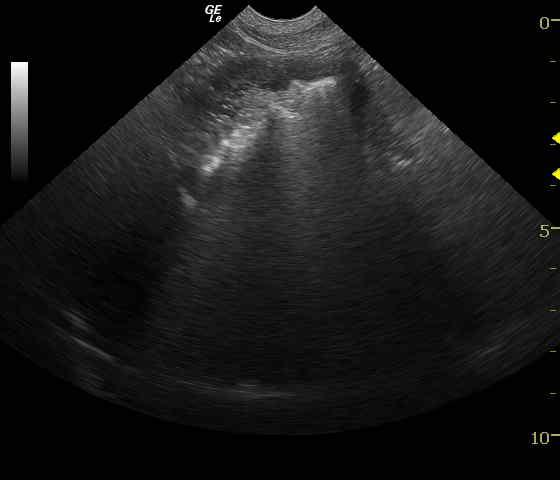

Gastrointestinal foreign body in a 6 year old FS Boxer

FB obstruction, pseudo obstruction, focal ulceration, inflammation with variable ultrasound echogenicity giving the appearance of a probable obstruction.

Hyperechoic relatively linear echo found in the pyloric antrum with continuation through the pylorus into the upper duodenum (image 1). There appears to be mild thickening at the proximal duodenum. Pyloric outflow view demonstrates progressively shadowing material embedded within the pylorus (Image 2). Hyperperistalsis is seen at the proximal portion of the bowel where this foreign obstruction was present (Image 3).